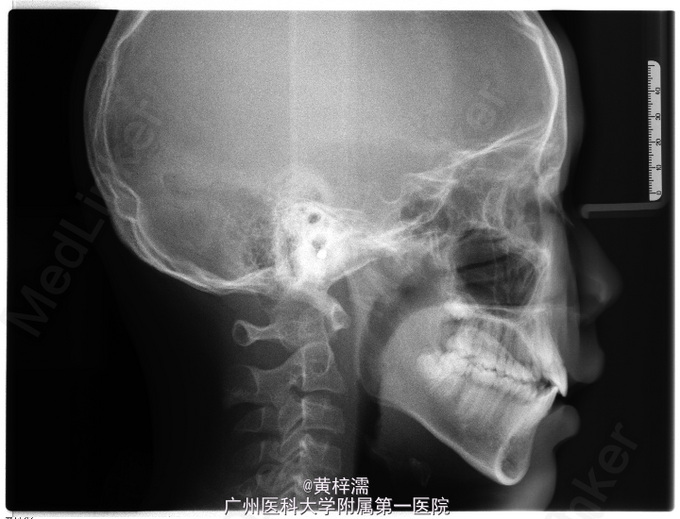

面部基本对称,无露龈笑,笑容不自然。直面型,面中1/3高度与面下1/3高度基本相等。下颌后缩,颏部发育稍不足。上中线与面中线一致,下中线稍右偏0.3mm。左侧磨牙关系中性,无尖牙关系。22,24间前庭沟下方可见鼓起,扪及23,磨牙覆盖正常。右侧磨牙关系中性,尖牙关系1/4远中,磨牙覆盖正常。上牙弓卵圆形,23缺牙间隙8.5mm,13宽度为8.5mm。口腔卫生可,未见牙体、牙周疾病,颞下颌关节检查未见异常。

诊断:安氏ǀ类错牙合;23埋伏阻生牙 处理:选择非拔牙矫治+23外科-正畸导萌术。全口固定正畸治疗,排齐阶段使用双丝技术牵引23,精细调整咬合关系及保持,总疗程18个月。

患者对治疗效果满意,拆除保持器维持1年。讨论:在判断阻生尖牙是否能自行萌出首先需判断阻生牙的倾斜角度及与侧切牙重叠位置,一般阻生超过侧切牙牙根1/2的阻生牙较难自行萌出,第二需要观察尖牙牙根发育状况而定。本患者尖牙已无自行萌出的趋势,因此行正畸牵引。 处理此类阻生尖牙时,首先粘接牵引附件需要确定牵引方向,控制牵引过程牙根不能碰及邻牙;其次牵引阻生牙时,牙列主弓丝必须时硬丝,利用短NITI丝段对阻生牙进行牵引,这样可以避免牵引过程对邻牙产生影响,稳定牙弓。第三,牵引后需要观察牙根方向和轴向,如不佳需要调整为好。